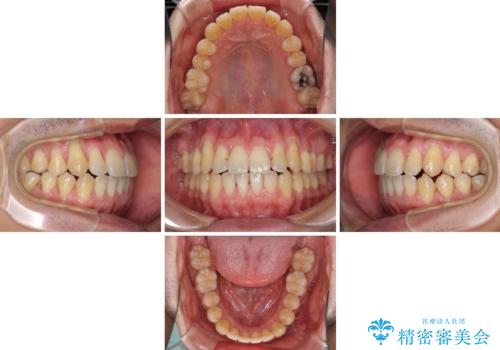

- 上下の前歯の反対咬合を気にして来院された患者様です。

インビザラインを用い、下顎はIPR(歯と歯の間を削る)と歯列全体を後方に移動させ、上顎は前歯を持ち上げることで、反対咬合を改善していくこととしました。

八重歯の歯根が見えている点も気になっているので、矯正歯科治療後に歯肉移植による根面被覆を行うこととしました。